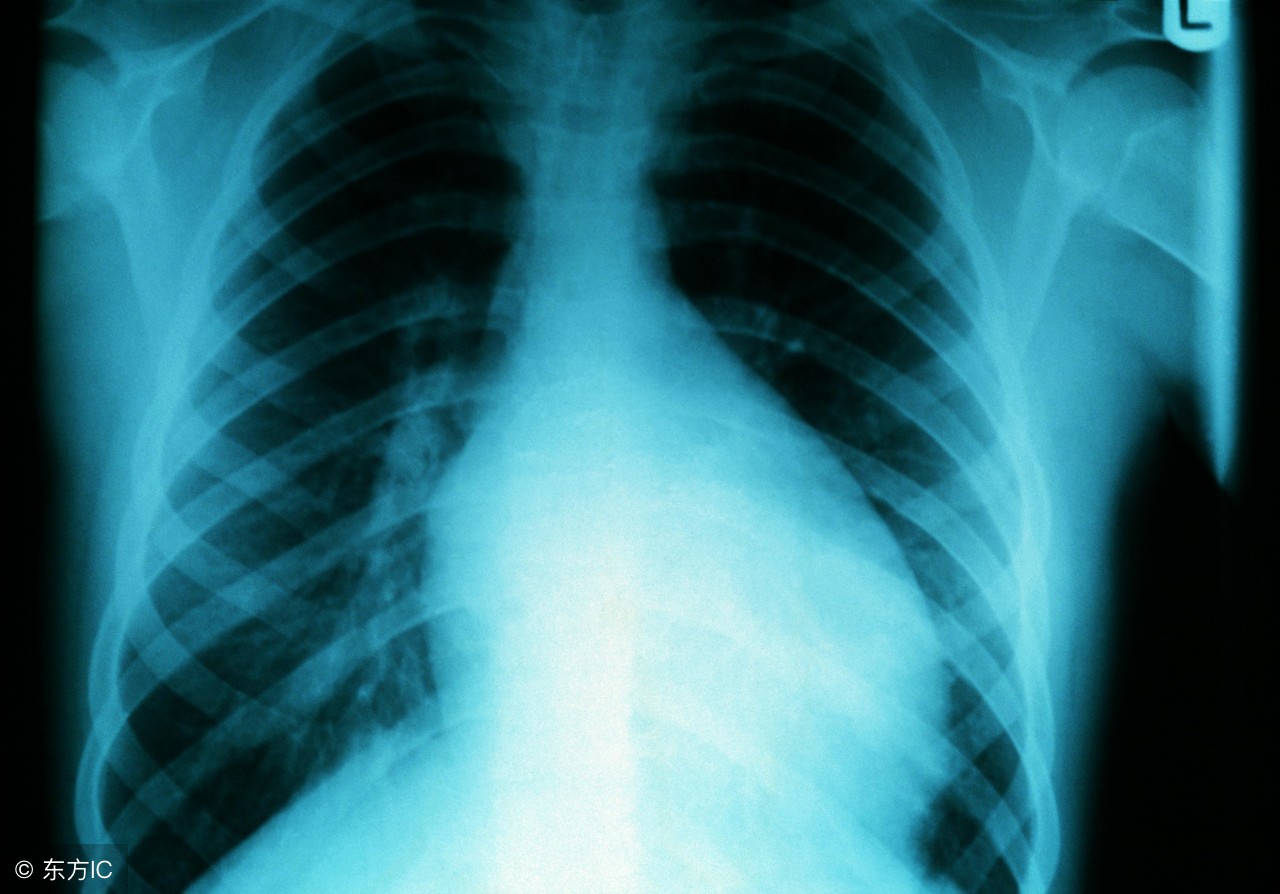

心肌炎的病因,心肌炎主要好发于中青年人群中,主要是病毒性心肌炎,一些中年人群长期处于学习压力和工作压力当中,饮食睡眠的不规律极易造成心肌炎的发病。心肌炎对我们的身体健康有危害很大,及时了解心肌炎的发病原因,做到有效的预防。心肌炎给我们的生活造成严重的影响,不要忽视了心肌炎对健康的危害。